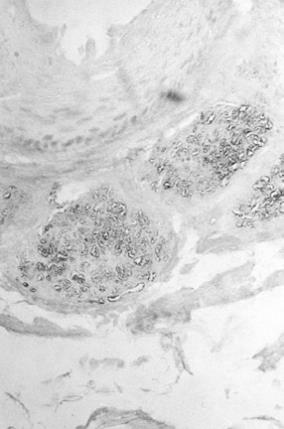

22. ábra. A cytokeratin a faggyú- és verejtékmirigyekben egyaránt kimutatható. Római kori múmia bőre. Pancytokeratin-ABP reakció, 100× nagyítás